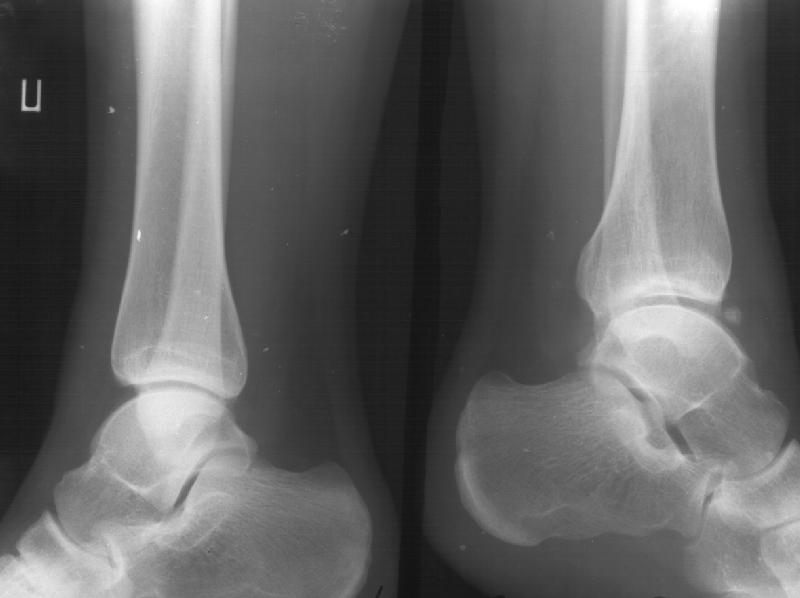

Отправитель: Alexander Chelnokov 19 Январь 2003, 22:34

Сегодня пациентке сделали сравнительную КТ. А ксиальные и Фронтальные срезы приложены. Ваше мнение?

Фронтальные

Аксиальные

Отправитель: Й. Воск 19 Январь 2003, 22:50

На КТ я попытался изобразить скромными своими способностями (А)- место перелома, (С)- нормальный суставной зазор меж тараном и тремя его маллеолами. (В)- образовавшийся в результате перелома широкий раза в три зазор, позволяющий, по-моему, сублюксацию тарана при ходьбе. В свете данных КТ, критически важных, я бы предложил вертикальную остеотомию места перелома

задне-внутренним подходом и фиксацию мед. маллеола прижатым к тарану с помощью тонкого compression screw. После этого гипсовый сапожок и немедленное расхаживание ноги.